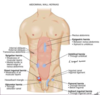

label this